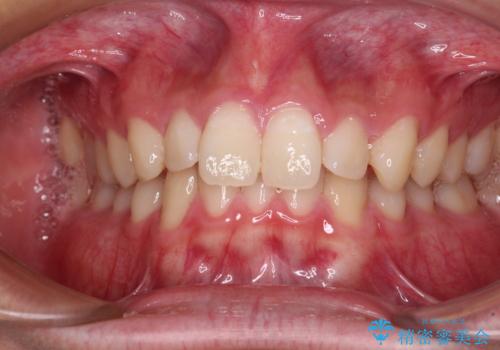

- 上下前歯のデコボコと深い咬み合わせを気にして来院された患者様です。

下顎前歯が一本欠損しており、下顎の歯列が小さいため、ディープバイトになりやすい状態でした。